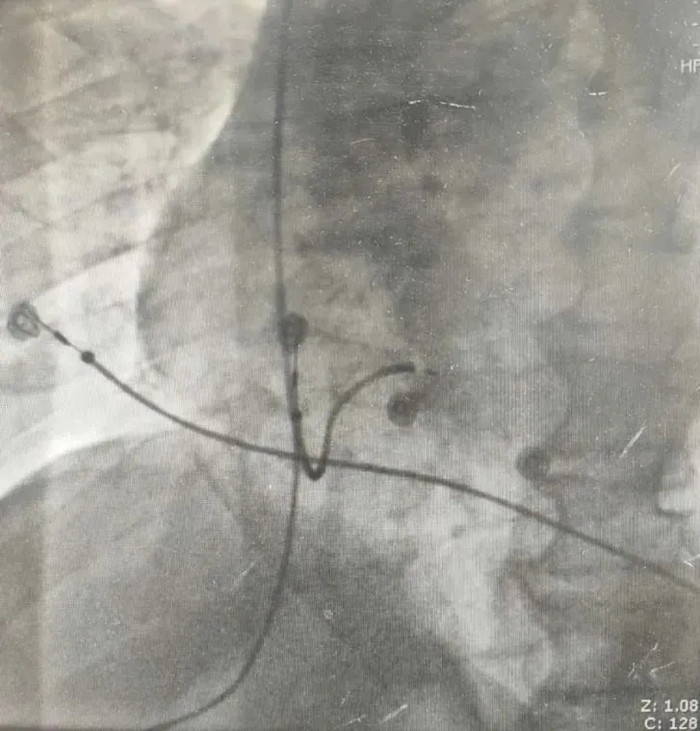

术前,心血管内科一、三病区的电生理团队充分讨论了手术方案和术中细节。由于心室电极的植入需要由右室间隔面旋入左室间隔面,术中需密切注意电极的深度及腔内图的变化,电极稍浅可能造成电极的不到位、不能起搏左束支,而电极稍深可能造成室间隔穿孔,“毫厘之差”便可造成手术的不成功;而且该患者是一名心衰患者,平卧时间不能过久,需要快速完成手术,进一步加大了手术的难度。手术由心血管内科一、三病区副主任、主任医师王占启和陈春红共同完成,凭借精湛的技术和过硬的心理素质,顺利完成了手术,手术历时90分钟,患者术后各项指标均良好,达到了理想效果。